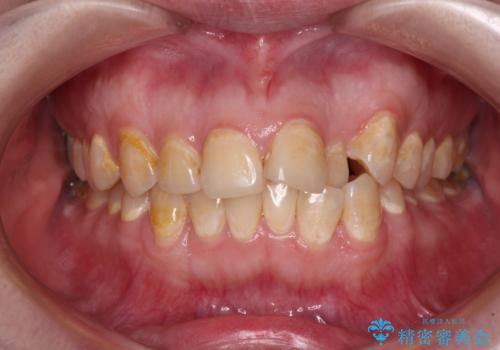

- 前歯のデコボコとクロスバイトが気になり、インビザラインによる矯正治療を希望して来院された患者様です。

上顎側切歯(上の真ん中から2番目の歯)が舌側転位している場合、無理して動かそうとすると歯髄壊死を起こすリスクが高い印象があります。

インビザライン単体でも治療は可能ですが、安全策としてインビザラインで歯列を移動する前に上顎前歯をワイヤー矯正で整え、その後上下歯列をインビザラインにて矯正治療を行うこととしました。